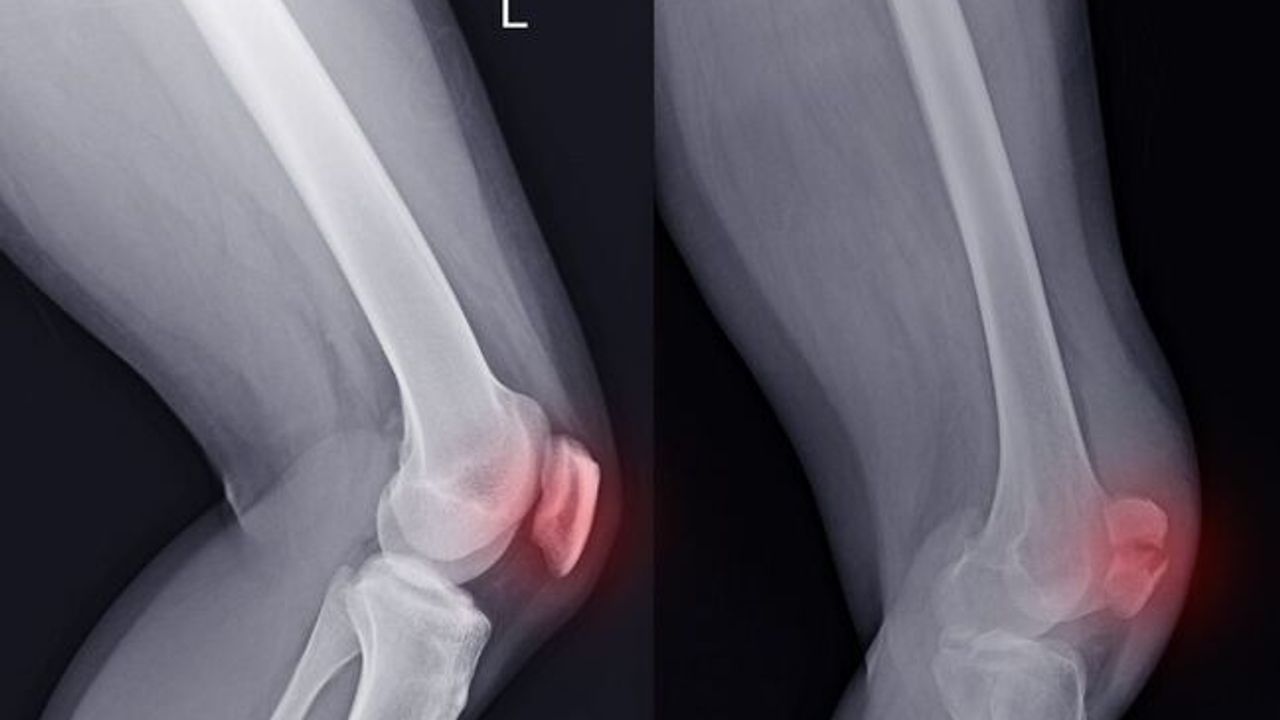

Spor sırasında ani bir diz dönmesiyle veya doğrudan dize gelen bir darbe sonucu ortaya çıkan keskin bir ağrı, şişlik ve şekilde bozukluk… Bu tablo, özellikle genç ve aktif bireylerin korkulu rüyası olan diz kapağı çıkması (patella çıkığı) durumunun en net göstergesidir. Diz kapağının, uyluk kemiği üzerindeki yuvasından dışarıya doğru kaymasıyla oluşan bu durum, acil müdahale gerektiren ve doğru tedavi edilmediğinde tekrarlayan sorunlara yol açabilen ciddi bir yaralanmadır.

● Görünür Deformite: Diz kapağının normal yerinde olmadığı, dizin dış tarafında bir şişlik olarak görüldüğü anormal bir görünüm.

● Şişlik: Çıkık sırasında eklem içi yapıların hasar görmesiyle dizde hızla gelişen şişme.